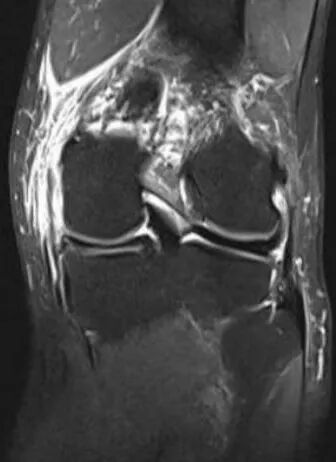

患者李先生,因外伤致左膝内侧半月板后角损伤(Ⅲ度),在腰麻下行膝关节镜下半月板缝合术,此次手术由陈功主治医师主刀,依托成熟的关节镜微创技术,在高清内镜引导下,仅通过2个微小切口便清晰显露损伤部位,运用专用缝合器械将撕裂的半月板组织精准对合、牢固固定,有效避免了传统切除手术可能带来的关节不稳、骨关节炎等远期风险。

青少年运动损伤到中老年人退行性撕裂,省荣康医院骨科团队始终以患者为中心,结合术前影像学评估与术中实时探查,为不同损伤类型、不同年龄的患者制定个性化诊疗方案。手术全程精准高效,术后搭配科室专属康复指导,帮助患者快速恢复关节活动度,多数患者术后1-3个月即可重获正常生活与运动。